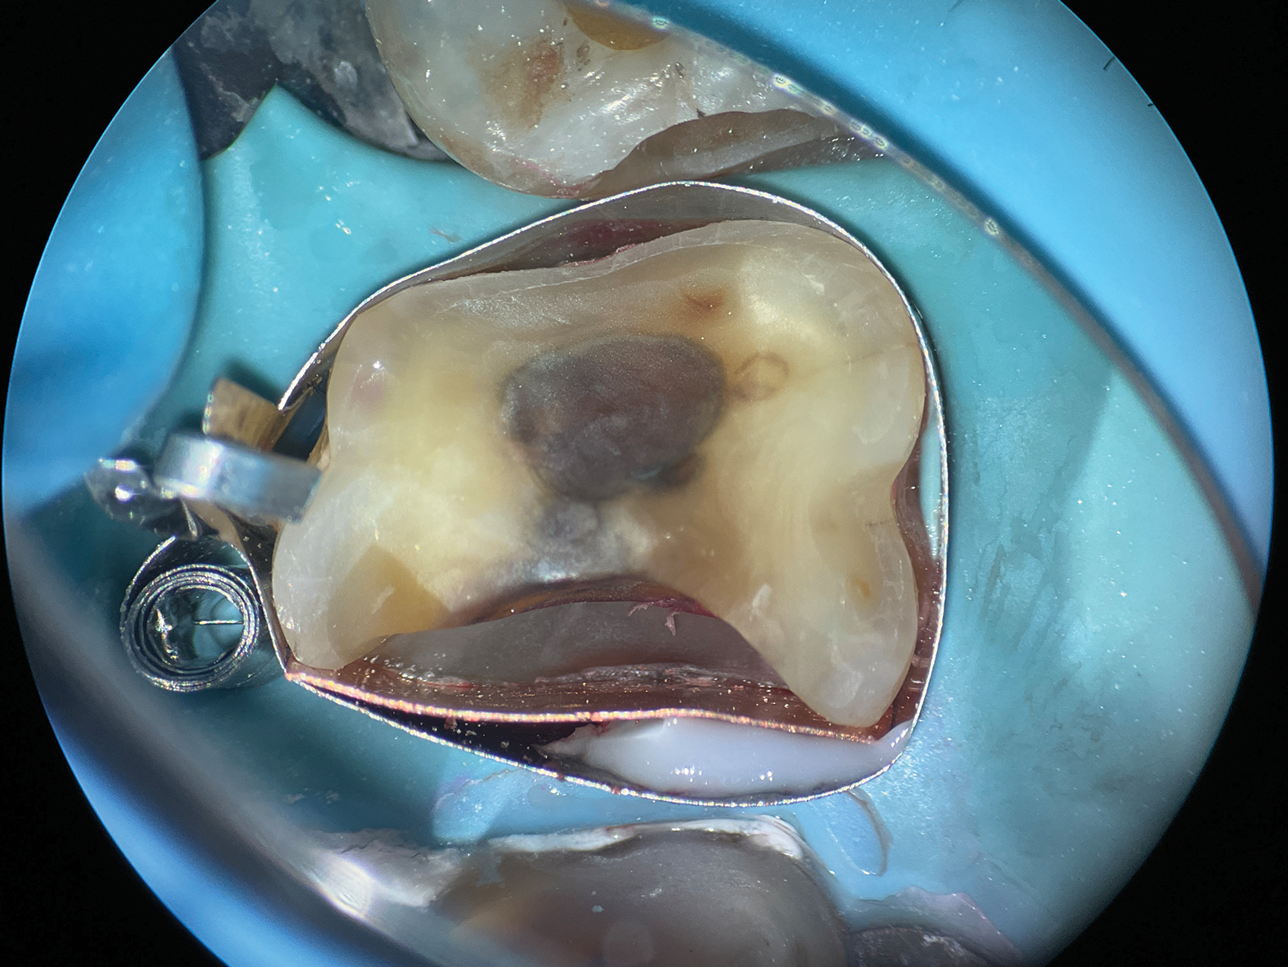

(8.) Close-up occlusal view of a maxillary first molar after the removal of deep subgingival caries, where despite rubber dam isolation, infiltration of blood and saliva into the cavity has occurred.

Figure 8

(9.) Close-up occlusal view of the maxillary first molar prepared for a matrix-in-matrix technique with a circumferential matrix supported by a 3-mil copper band inside for proper adaptation to the margin’s concave and convex areas. Note the addition of a liquid dam material placed between the two matrices for added stability.

Figure 9